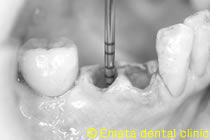

周りの骨を壊さないように慎重に抜歯したところです。

抜歯と同時にインプラント埋入、無切開で行く予定で、抜歯の部位とドリルを合わせています。

外側の骨が欠損しているのがわかりました。